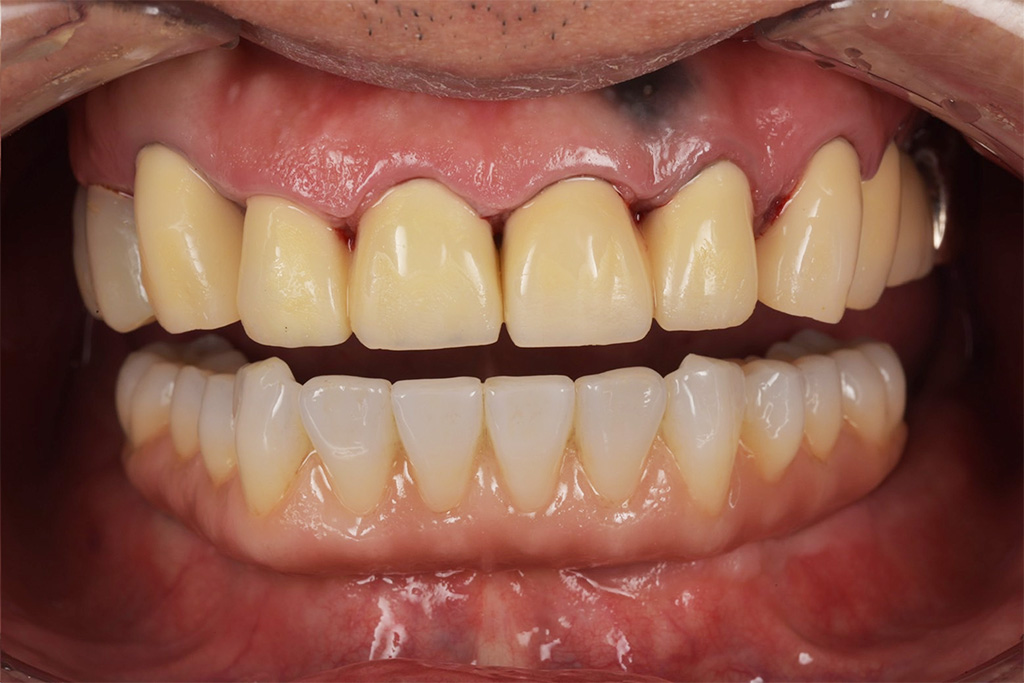

今回は噛めることと見た目の改善を目的として上顎はダメな部分は抜歯をし、インプラントを入れました。

現在では硬いものもかめてやってよかったと言われて私は満足しかありません。

かなりボロボロでもこのような難症例であろうと私は治療ができると自信がつきました。

今では定期検診でしっかりと予防を行っていただいています。